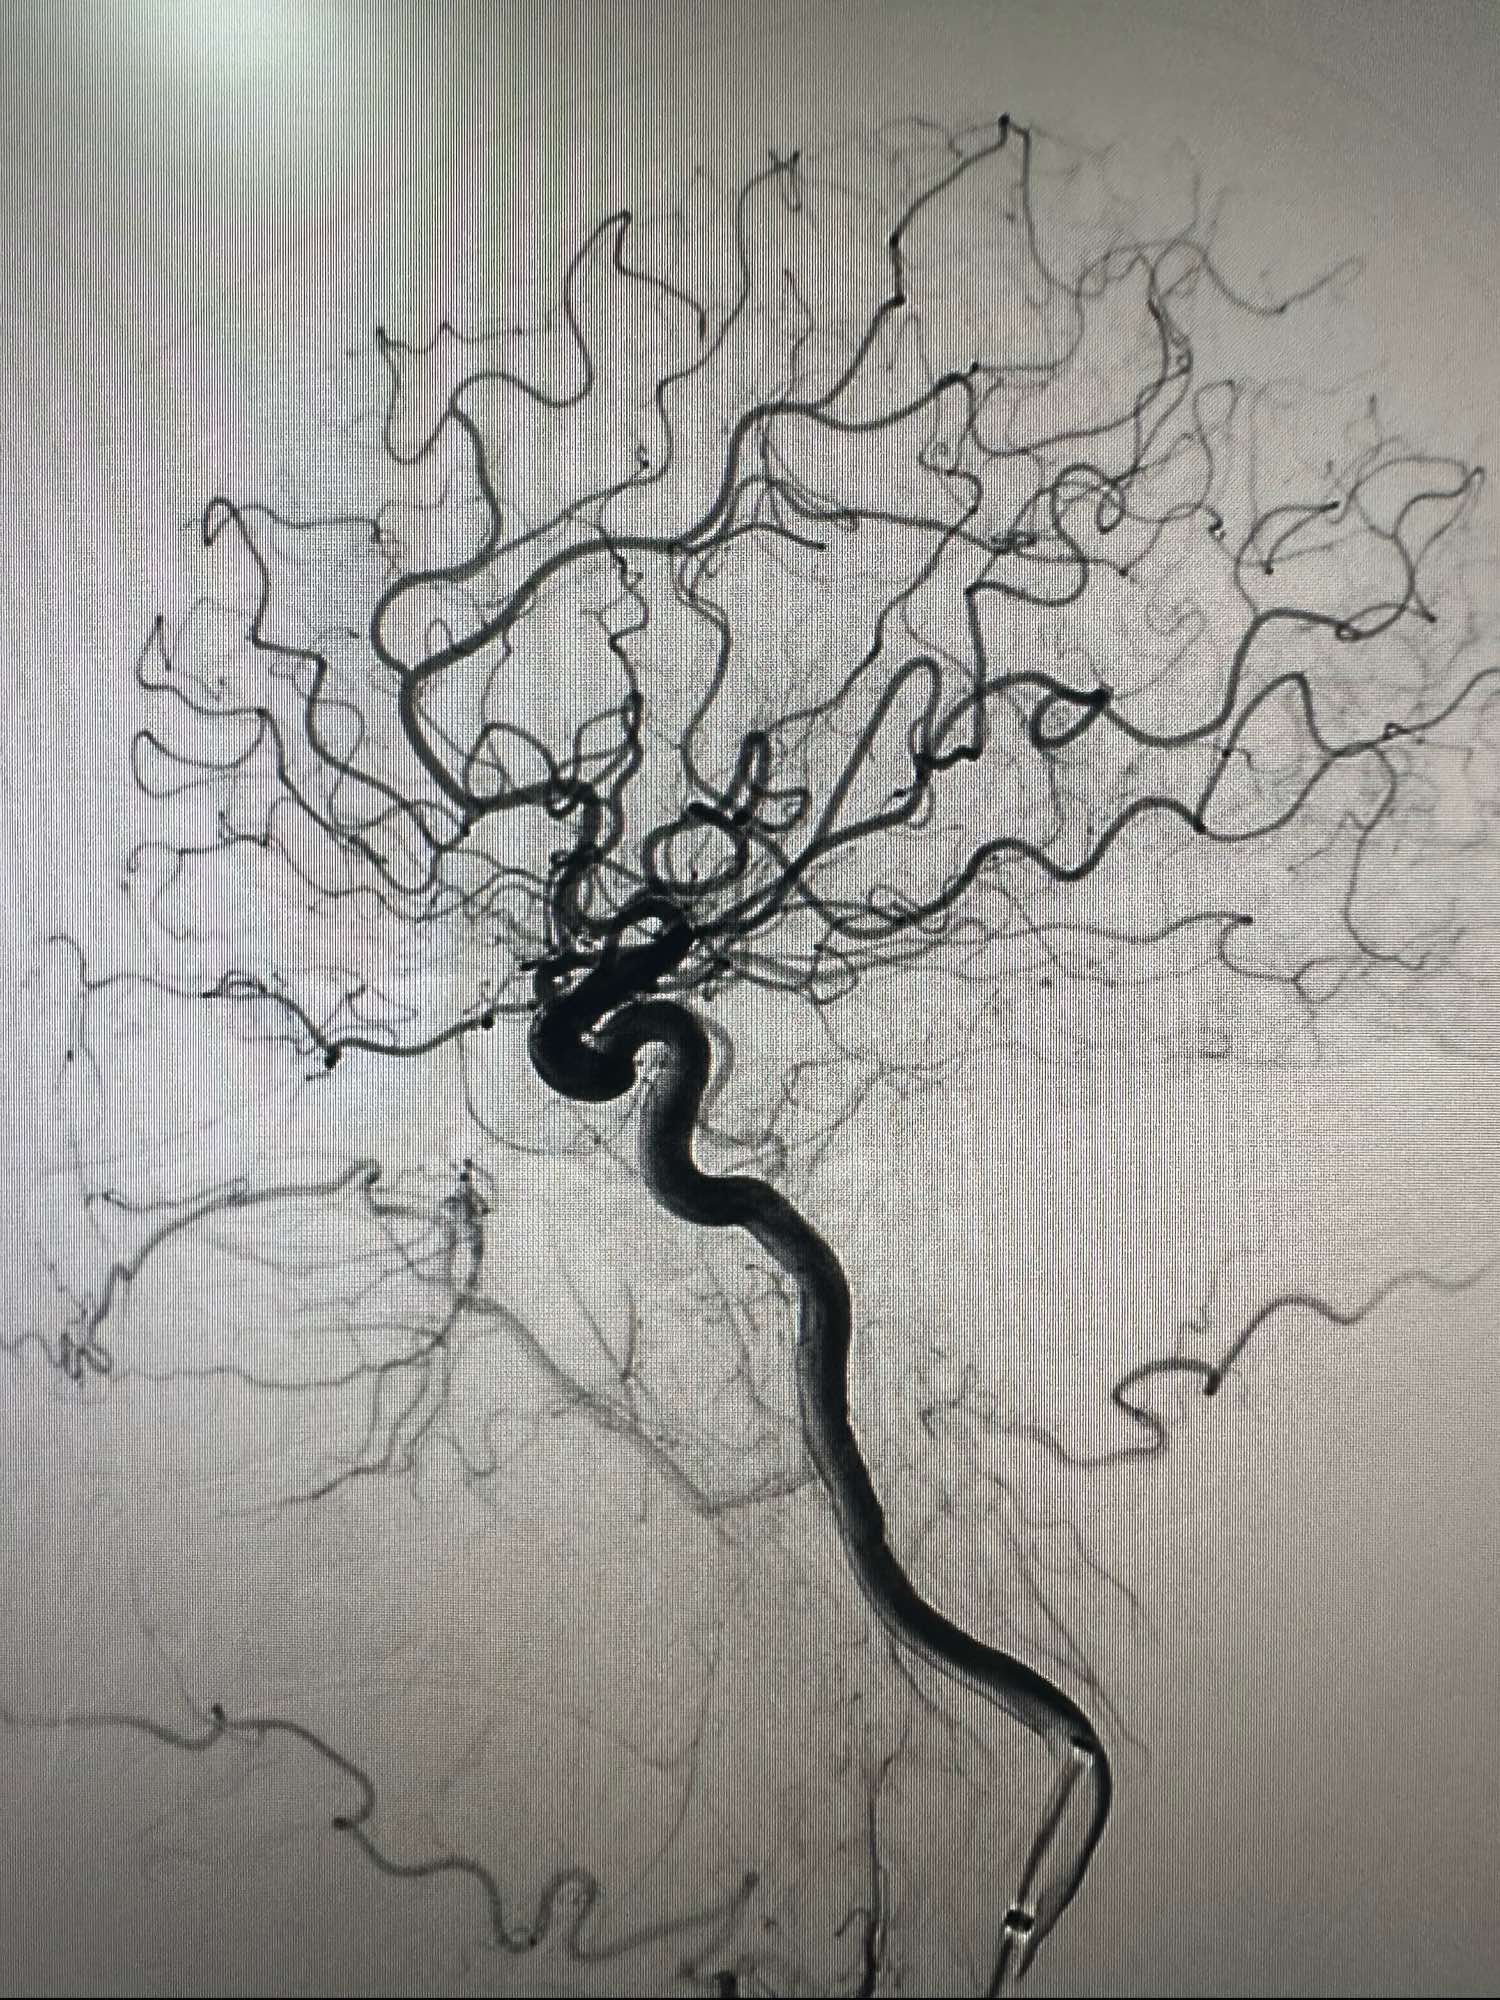

右侧颈内动脉造影正位